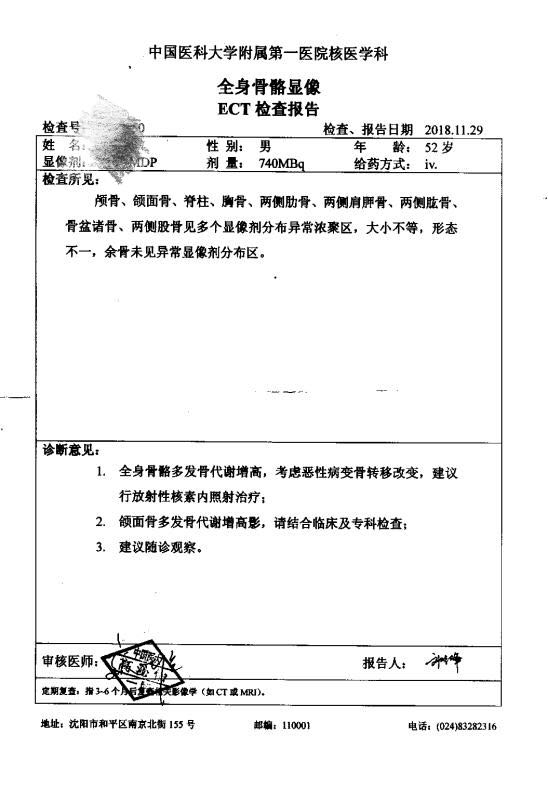

晨光1226 02019-03-13 患者家属我父亲52岁,在我过生日那天确诊胰腺癌晚期,并骨转移,肝转移,医院不建议化疗,无法手术,住院15天后医院不留,拿着片...